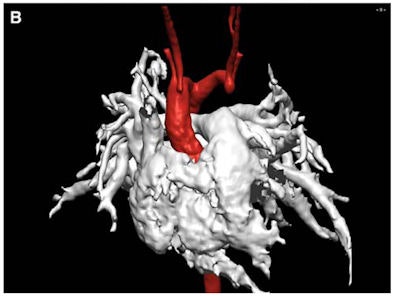

| This infant patient presented with tracheal stenosis due to a double aortic arch with an atretic left anterior part. Transverse turbo spin-echo images display the tracheal stenosis by the right aortic arch as seen in image A (top). A 3D volume-rendered reconstruction of the double aortic arch with the atretic left anterior arch is shown in image B (bottom). Each arch gives rise to the ipsilateral common carotid and subclavian artery. Images courtesy of Pediatric Cardiology. |